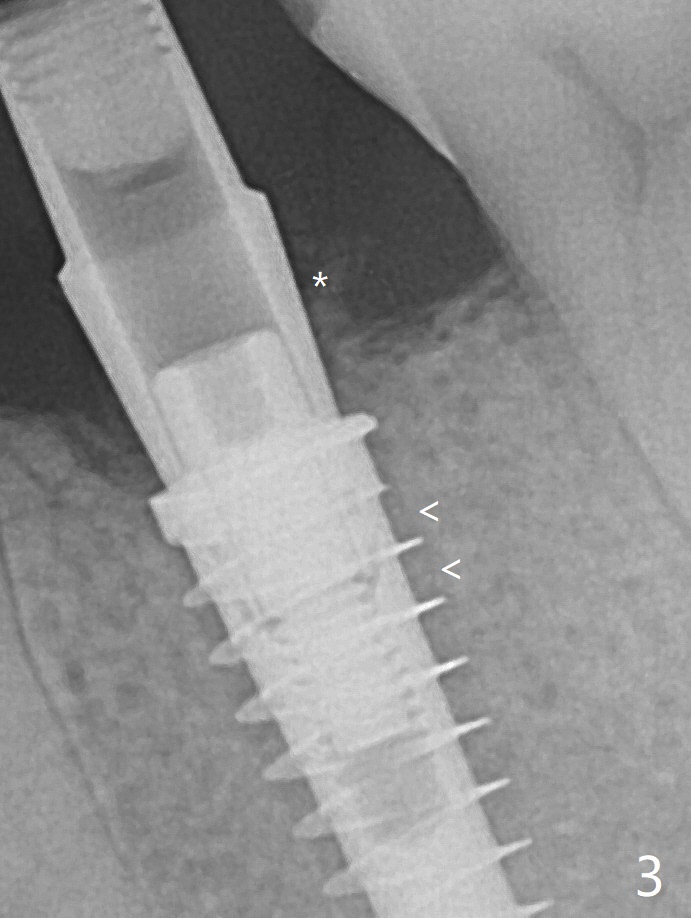

放置基台前,骨粉放置低于植体上端(Plateau),但是远中仍有间隙(图二箭头)。 放置基台后,两度填骨粉(图三*),远中间隙仿佛消失(箭头)。术后两个月,植体顶端似乎被牙槽嵴覆盖了(图五)。